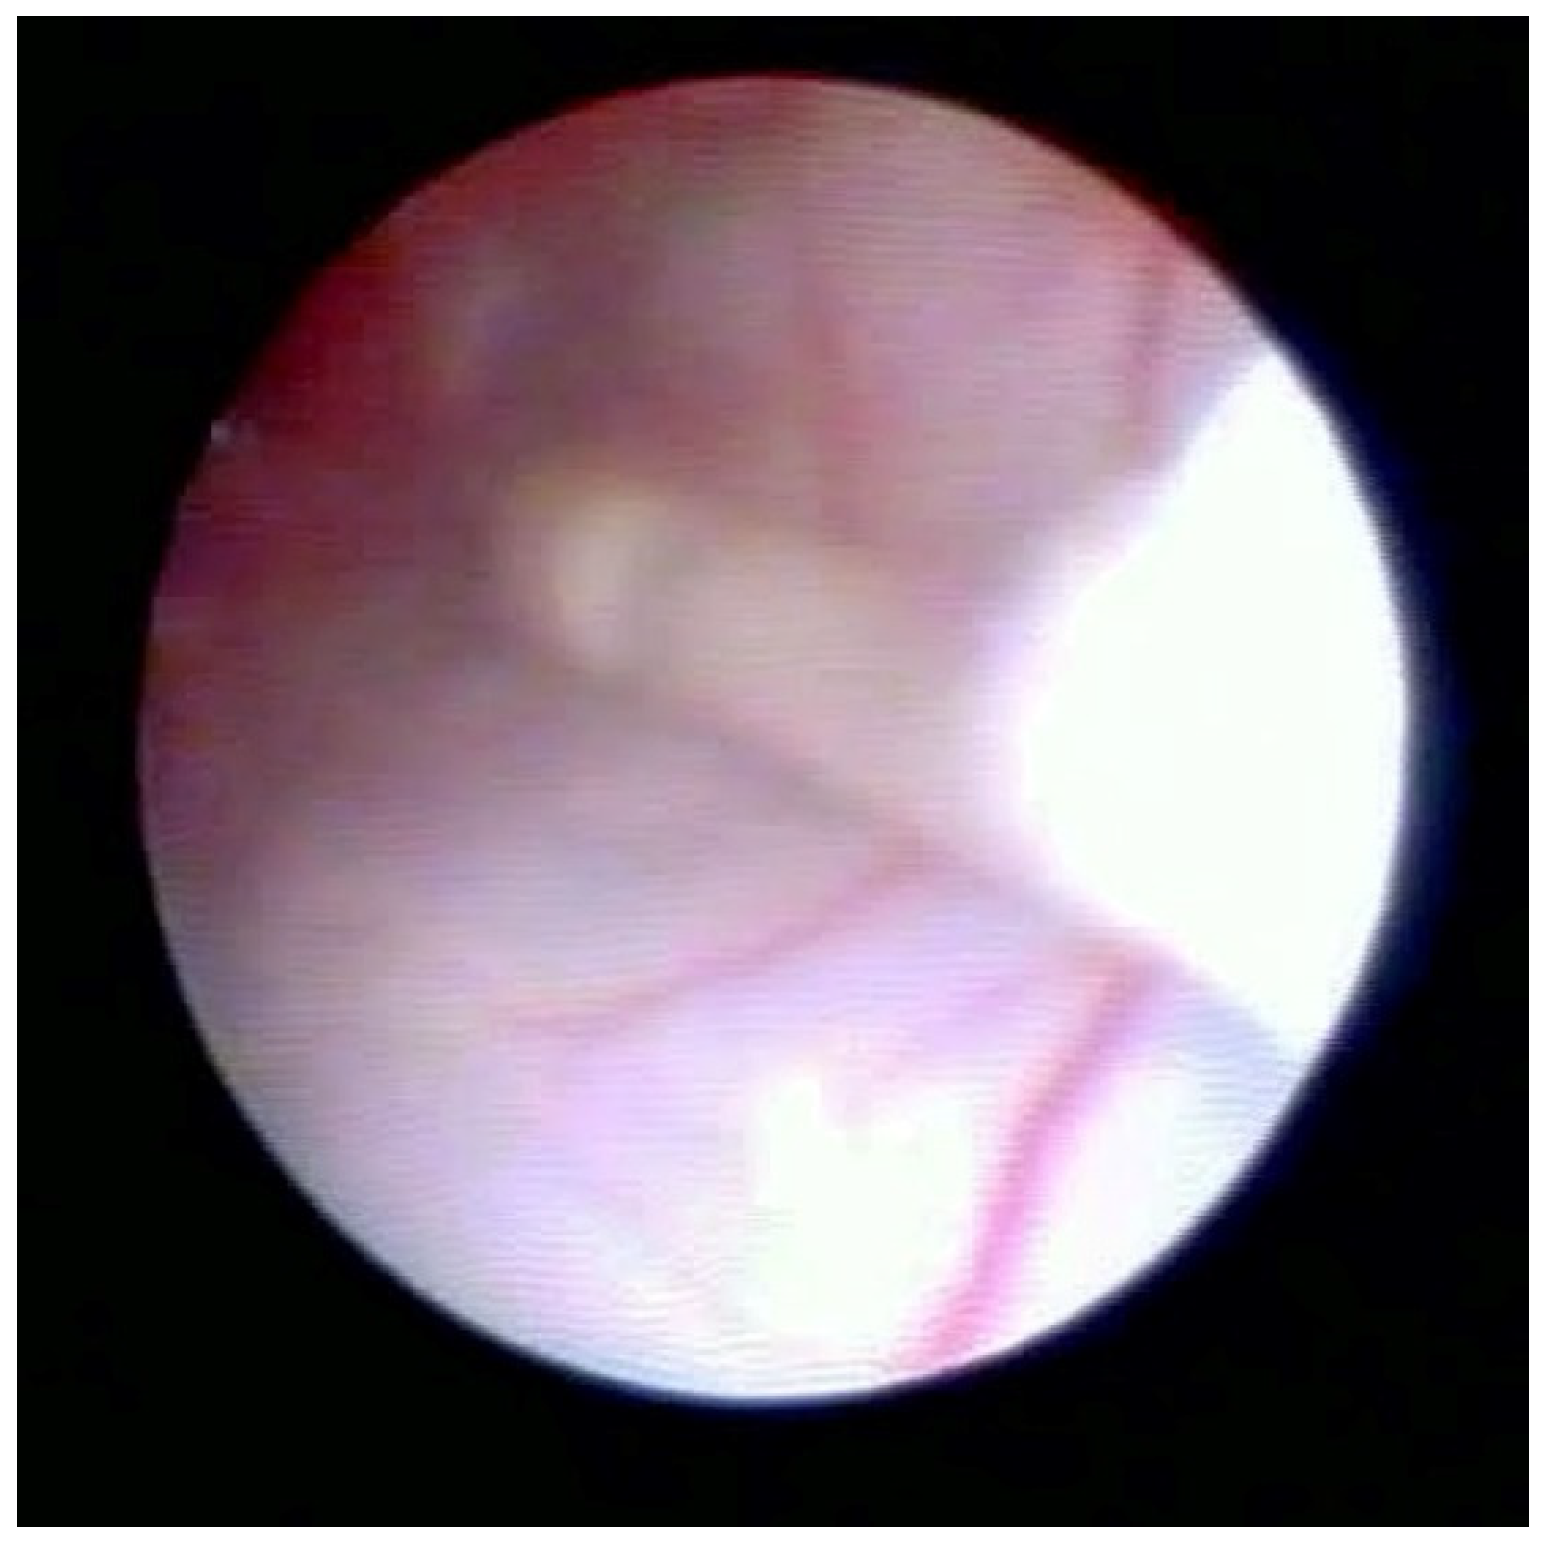

Figure 2 shows the lifting of the meningeal dura for dural mobility abnormalities with an underlying lifting of the spinal root, which determines a pseudo-lifting of the dura, potentially resulting in a false diagnostic radiology interpretation of a median ligament. Moreover, the presence of a Fogarty catheter inside the bed of the dura in the midline causes lifting of the dura mater in relation to the root below, which can mimic a false longitudinal ligament in radiodiagnostic imaging (Figure 3). Morphological analysis of the pathological spaces also showed that, in these cases, no segmentation occurred. The left side of Figure 4 shows a fibrotic septum grafted on the dura. However, underlying dural bases exhibit no segmentation.

The presence of fibrotic septa, without apparent cause and limited to a single vertebral body, was detected in a few cases. In our video review, we found one patient with a segmentation-like feature. This appeared to be the result of a raising of the dura due to loss of its elasticity and the presence of a hyperpressure on the dural cloth (Figure 2), as previously reported [16].

Figure 2. Normal dura, root lifting.